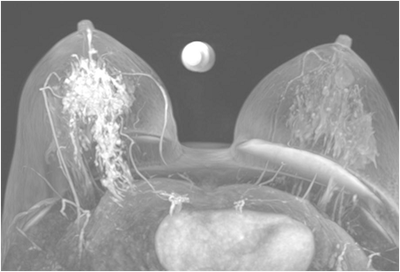

52 year old lady who underwent wide local excision for stage I breast...

Read More